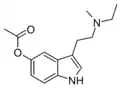

| 5-AcO-MET [9] | artificial | 5-OCOCH3 | CH3 | CH2CH3 | 5-acetoxy-N-methyl-N-ethyltryptamine | |